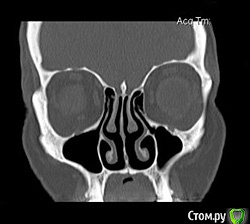

Kostoprav Опубликовано 26 апреля, 2015 Поделиться Опубликовано 26 апреля, 2015 Всем доброго времени суток коллеги!Проблема в следующем- высокая септа и мукоцеле на медиальной стенке пазухи.Мой план: сделать два окна в пазуху по обе стороны от перегородки, аккуратно попробовать отслоить слизистую и если получиться не порвать ее установить два болта не трогая кисту. В случае тотального разрыва мембраны спилить перегородку, убрать мукоцеле, зашить пазуху и повторно пойти на синуслифт через 2 месяца.Хотелось бы услышать Ваши варианты дорогие коллеги. 1 Ссылка на комментарий

Alexey Doc Опубликовано 26 апреля, 2015 Поделиться Опубликовано 26 апреля, 2015 Покажите пожалуйста соустье справа. На этих срезах видно только слева Ссылка на комментарий

Alexey Doc Опубликовано 28 апреля, 2015 Поделиться Опубликовано 28 апреля, 2015 При просмотре КТ еще обращаю внимание на состояние решетчатых воронок, зачастую при их окклюзии есть проблемы в пазухах.на картинке цифрой 3 обозначена. Если патологии не видите то по тактике согласен, если есть вопросы то консультация Лора 1 Ссылка на комментарий